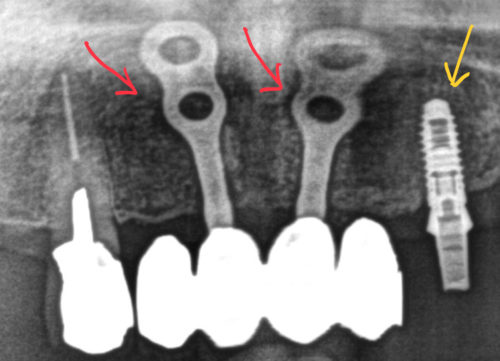

インプラントはオペの回数と構造で2種類に分かれます

赤:1回法

黄:2回法

1回法はオペが1回なので簡単ですが、被せ物の形や清掃性が2回法のそれに劣ります

本院では、よりインプラントが長く持つように、より見た目が良くなるように

2回法のみを選択しています

また1回法では要介護状態などになった時に、様々な点で良くないとも言われています